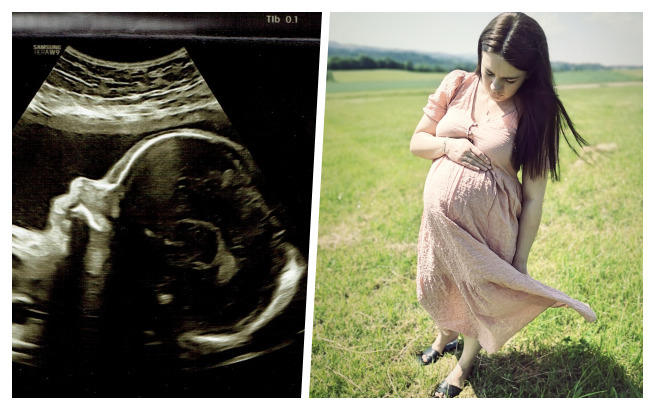

Radość oczekiwania przerwana brutalną diagnozą. Łucja w brzuchu mamy jest bezpieczna, ale tuż po przyjściu na świat rozpocznie dramatyczną batalię. Musimy zrobić wszystko, by pierwszy oddech naszej córeczki nie był ostatnim. Pomocy!

Trzecia ciąża, trzecia pociecha, pełne emocji oczekiwanie całej rodziny. Kolejna standardowa wizyta u lekarza, która na zawsze zostanie w naszej pamięci. Początkowo usłyszeliśmy o podejrzeniu nieprawidłowości, ale to uruchomiło całą machinę: strachu, kolejnych konsultacji, rozpaczliwego poszukiwania ratunku. Nadziei, która nie opuściła nas do dzisiaj.

Diagnoza - krytyczna wada serca - stenoza aorty z restrykcyjnym otworem owalnym odwróciła nasze życie do góry nogami.